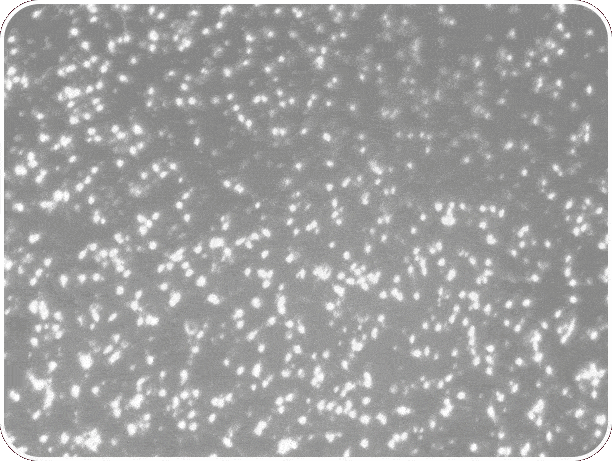

| Spermiogram teszt eredmények | |

| PROfertil® szedés előtt A spermiogram fontos vizsgálati módszer a férfi termékenység felmérésére. Az értékelést a WHO (Egészségügyi Világszervezet) irányelveinek megfelelően végzik. | PROfertil® szedés után A spermiumok koncentrációját, mozgékonyságát, mennyiségét, illetve alakját vizsgálják mikroszkópos eljárással |